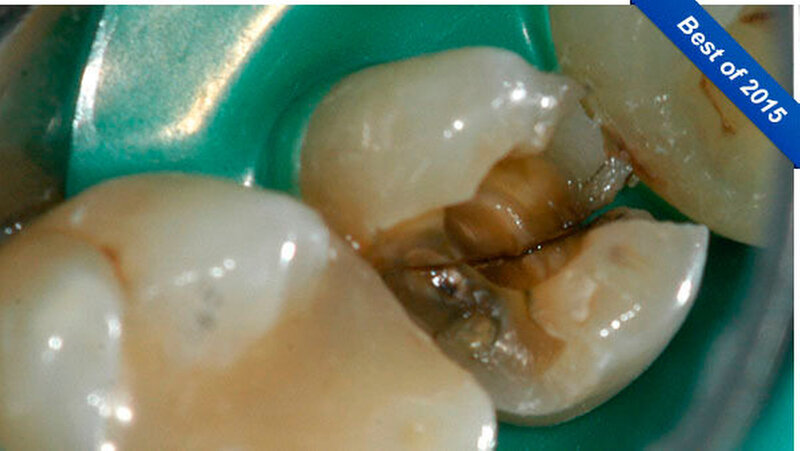

In der Poliklinik für Zahnerhaltung des Universitätsklinikums Münster war zwar die allgemeinmedizinische Anamnese unauffällig, doch zeigte sich klinisch nach Entfernung der vorhandenen mod-Glasionomerzementfüllung ein deutlicher Frakturspalt in mesial-distaler Ausrichtung am Boden der Kavität (Abbildung 1). Darüber hinaus war auf der Röntgenaufnahme des Vorbehandlers eine apikale Aufhellung zu erkennen (Abbildung 2).